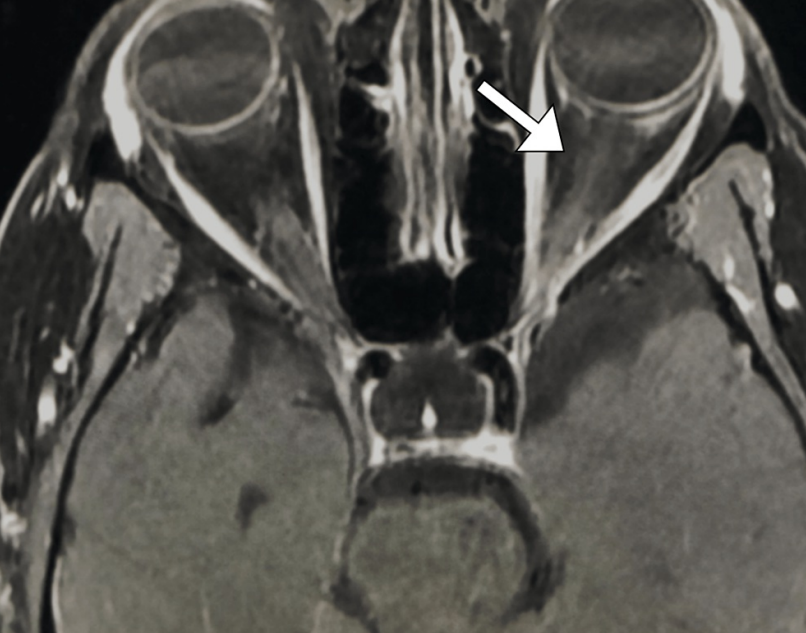

病史摘要:83 岁老年男性,因“前额疼痛性红斑性皮损持续一周”至急诊科就诊,初诊丹毒,口服克林霉素。一天后疼痛加剧,前额及左眼周围出现水疱性皮损,转诊眼科。患者曾因青光眼使用降眼压滴眼液。诊疗过程:眼部检查未见玻璃体或视网膜血管炎,Hutchinson 征阴性。诊断为眼带状疱疹(HZO),给予口服伐昔洛韦。次日出现复视,检查发现左眼内收等受限伴眼睑下垂。眼眶 MRI、脑 MRA 及